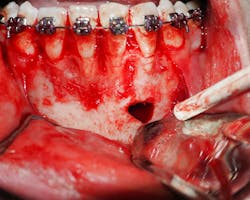

In this case, the patient underwent surgical exploration of the mandible. The lesion was mostly empty, though some tissue was submitted to pathology (figure 5). The tissue came back as fibrous connective tissue with some neural and vascular cells. The patient did well postoperatively.